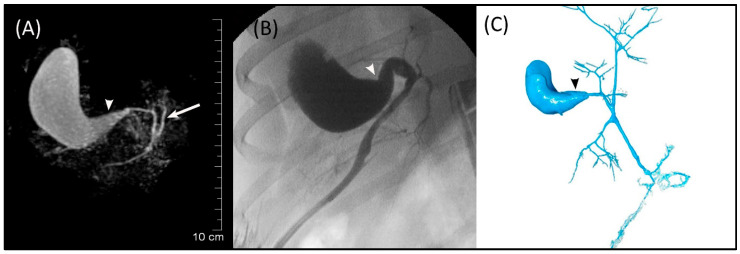

3.2. Visibility and Measurements

The GB (fundus, body, and neck), cystic duct, and CBD (at papilla and at extrahepatic ducts’ junction) were visible in MRCP, FRCP, and corrosion casting in all eight dogs. Visual comparisons between MRCP, FRCP and corrosion casting in Dog 6 with no evidence of disorders and Dog 8 with biliary disorders are shown in Figure 2 and Figure 3, respectively. The extrahepatic ducts and pancreatic ducts were variably visible in the MRCP and FRCP images. This did not allow for statistical analysis, only descriptive assessment.